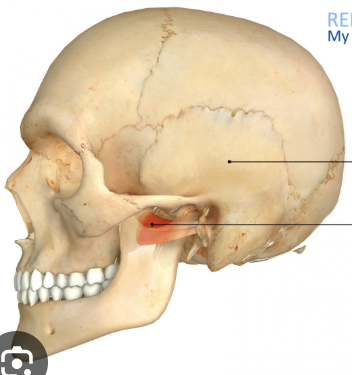

hamulus

small hooklike projection that extends from medial pterygoid plate

radiopaque, may be seen